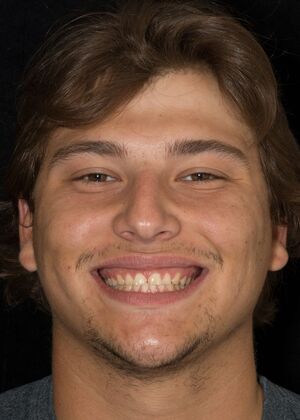

Porcelain Veneers: JG

Description: This young patient had wore down his front teeth due to persistent teeth grinding. Recognizing the importance of preserving the remaining teeth and restoring their aesthetics, he opted for early intervention. Four Porcelain veneers were fabricated and permanently bonded to his teeth.

Procedures : veneers

Testimonial : “These totally look like my teeth! And they feel super natural. Thank you for the terrific job Dr. Li!”